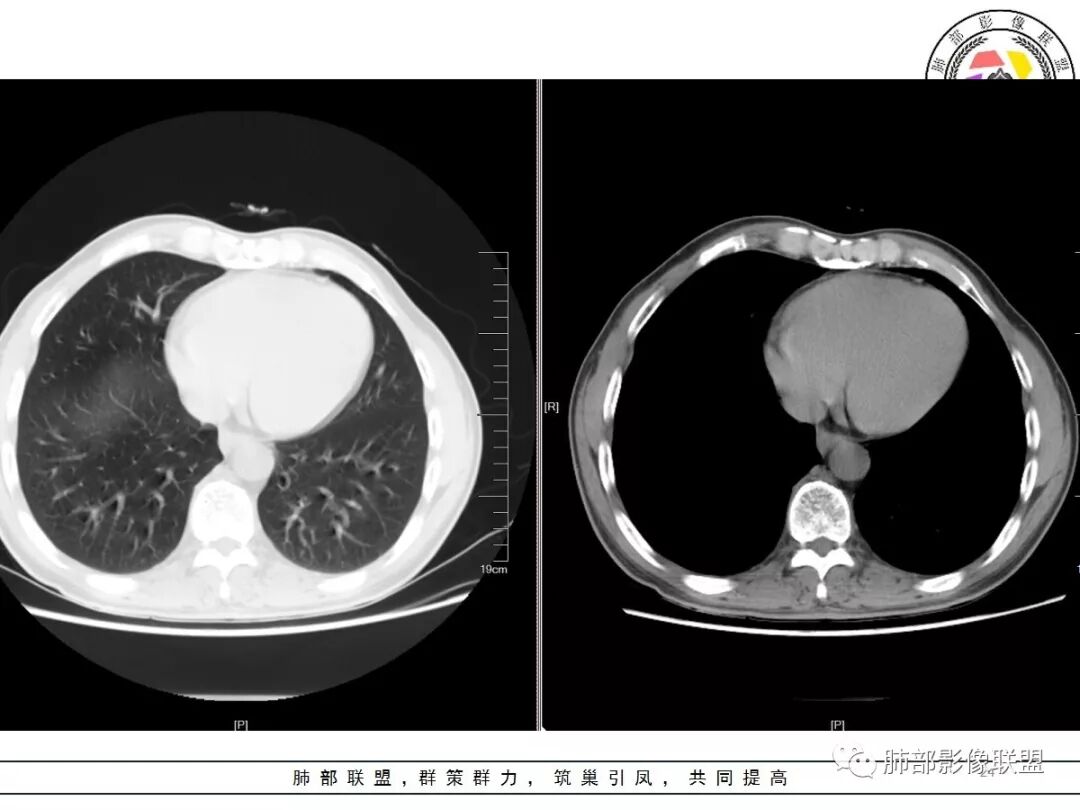

老年男性,体检发现,右肺上叶尖段类圆形结节

小叶中心型肺气肿背景,一般提示吸烟

周围有类似小结节

小斑片

根据周围常规:我们要考虑结核的可能

我们再看右肺上叶这个较大病灶主体

类圆形,浅分叶

胸膜凹陷

血管纠集

局部凸起

强化幅度超过20HU

边缘平直

南边:

有炎性的特点,但是确实存在恶性征象

我觉得恶性最起码不能排除,要考虑,最起码要建议临床干预

一般我的观点:多发炎性征象,如果合并有恶性征象,就不能排除恶性

1.应该是双肺上叶多发结节,散在大小不等,密度不均,左上纵隔旁病灶环形强化,似乎都符合结核灶。

2.焦点在乎右肺上叶那个有点另类、有点儿一本正经的结节,密度均匀,未见支气管进入,部分圆隆浅分叶,长毛刺或棘状突起,胸膜有点牵拉,像个特立独行的新生物吗?

3.最不支持腺癌的一条是强化程度太轻。此外分叶不典型,还有那条牵张于肺表面的长长的细线影,不大像是在牵拽。

4.小结节新生物不大容易观察到液化坏死,如观察到液化坏死更容易想到的也是结核。